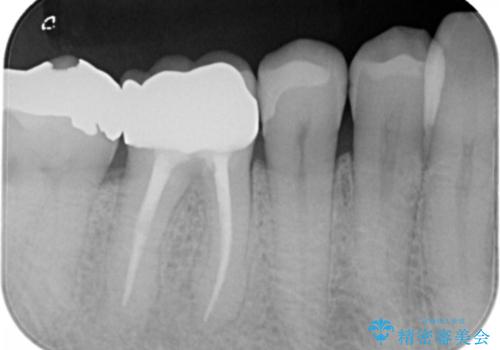

保険材料をセラミックにやり変えたい セラミックインレー

- 保険で治療された右下5番をセラミックにやり変え希望の患者様です。

切削量などを考慮し、セラミックインレーでの治療を選択しました。

古い材料と虫歯を全て除去した上で形成・印象を行い、セラミックインレーを装着しています。